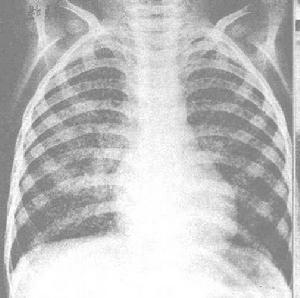

診斷:老年終末期肺炎大多數缺乏典型症狀和體徵,診斷主要依據肺部X線,有小片狀陰影,結合肺部可聞及水泡音,即可診斷。

2.影像學 終末期肺炎由於症狀、體徵不明顯,故診斷主要依據X 線,多顯示小片狀陰影,沿支氣管走行,右下肺為著,但臨床上也可聽到肺部可聞及明顯的水泡音,而胸片炎症徵象不明顯者,可能與長期臥床、炎性分泌物積聚到脊柱旁導致炎症陰影顯示不清有關。除此以外如合併心衰可見心影增大,並可見胸腔積液徵象,其原因考慮由於胸膜炎症反應,低蛋白血症及心衰綜合因素所致。